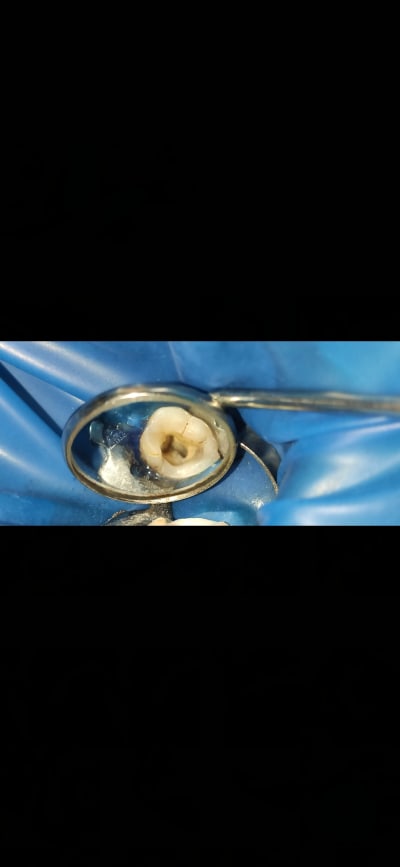

Resultat de mon endo

Obturation composite direct

EndoNoob écrivait:

superbe anatomie occlusale :)

c est la restauration définitive ?? a mon avis ca va casser assez vite...

Tu as quand même recomposé les 2/3 de la couronne en compo.